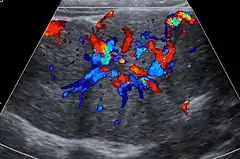

Unenhanced CT or MRI usually does not show the difference in intensity between the FNH and surrounding liver except when there is marked liver steatosis that reduces the attenuation of the liver, causing FNH to be hyperattenuating when compared with the surrounding liver. In the arterial phase CT or MRI, there is a strong enhancement not followed by washout. The lesion presents a slight hyperintensity or isodensity on portal venous phase or delayed phase images. There is also a presence of a central scar and absence of a capsule for the FNH.[5]

The prevalence of FNH of individuals undergoing evaluation with an ultrasound of the abdomen is 0.03%.[6] About 20% of FNH lesions are associated with hepatic hemangiomas.[6]